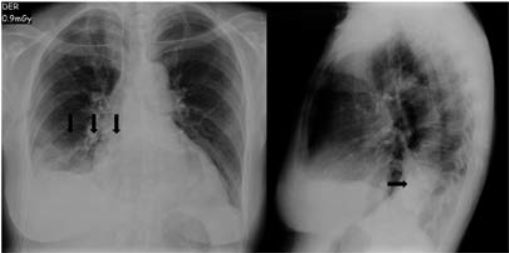

Posterior al comienzo del manejo médico, se observó una evolución clínica estacionaria con aumento de los requerimientos de O2 suplementario hasta requerir un alto flujo mediante el sistema Ventury al 50 %, con taquicardia persistente y dolor pleurítico, por lo que se plantea como posibilidad diagnóstica una embolia pulmonar aguda, razón por la que realiza angiotomografía de tórax (angio TAC), el cual corrobora el compromiso trombótico sobre la rama lobar derecha y de las segmentarias en el lóbulo inferior derecho (figuras 2).

AngioTAC de vasos de tórax Nota explicativa por imagen: (A) ventana angiográfica horizontal donde se observa el compromiso trombótico de la arteria pulmonar derecha; (B) ventana angiográfica frontal donde se observa la presencia de material trombótico que ocluye el flujo de la arteria pulmonar derecha y de su rama al lóbulo inferior derecho, además de infarto pulmonar en segmento posterior de lóbulo inferior derecho; (C) ventana de vasos pulmonares donde se observa el defecto de paso de medio de contraste a vasos pulmonares de lóbulo inferior derecho.

Figuras 2: AngioTAC de vasos de tórax Nota explicativa por imagen: (A) ventana angiográfica horizontal donde se observa el compromiso trombótico de la arteria pulmonar derecha; (B) ventana angiográfica frontal donde se observa la presencia de material trombótico que ocluye el flujo de la arteria pulmonar derecha y de su rama al lóbulo inferior derecho, además de infarto pulmonar en segmento posterior de lóbulo inferior derecho; (C) ventana de vasos pulmonares donde se observa el defecto de paso de medio de contraste a vasos pulmonares de lóbulo inferior derecho.